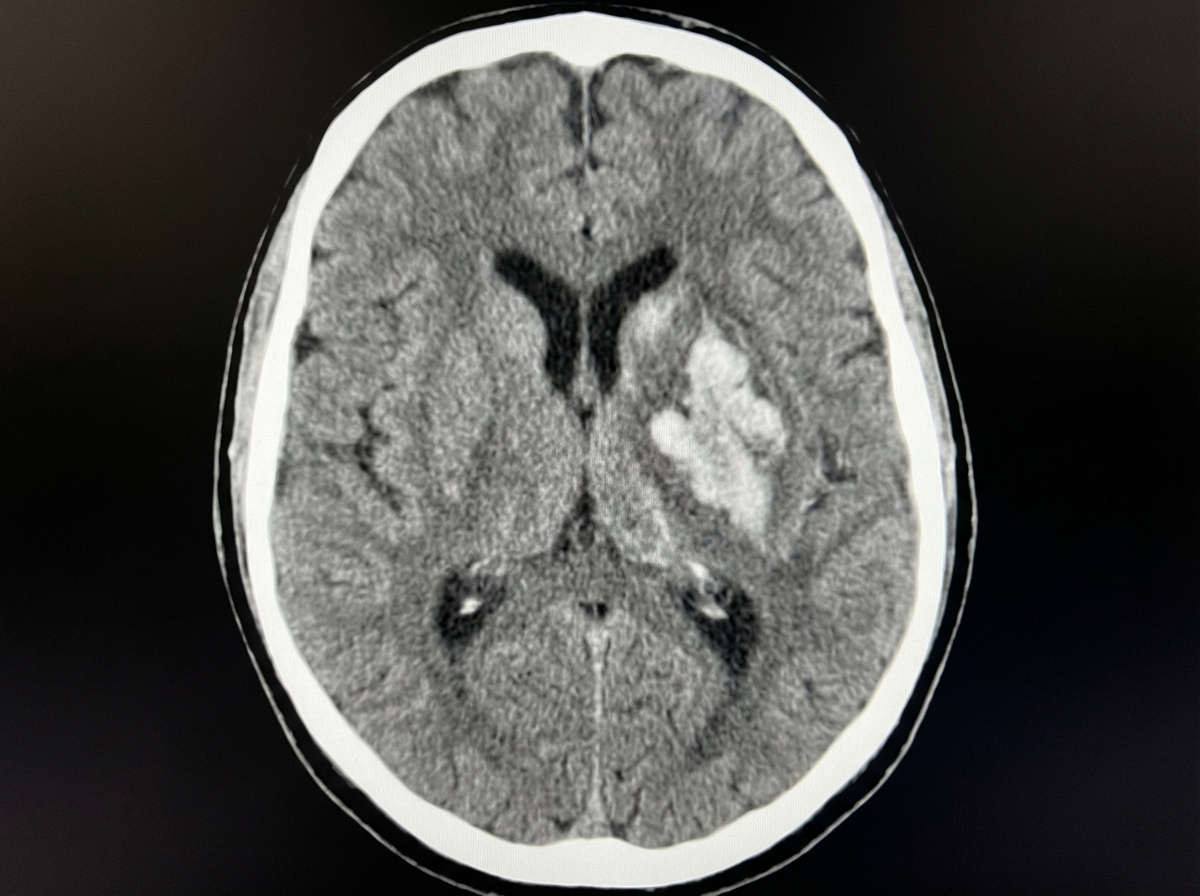

A 68-year-old woman is brought to the emergency department after being found unresponsive in her bedroom in a nursing home facility. Her past medical history is relevant for hypertension, diagnosed 5 years ago, for which she has been prescribed a calcium channel blocker and a thiazide diuretic. Upon admission, she is found with a blood pressure of 200/116 mm Hg, a heart rate of 70/min, a respiratory rate of 15 /min, and a temperature of 36.5°C (97.7°F). Her cardiopulmonary auscultation is unremarkable, except for the identification of a 4th heart sound. Neurological examination reveals the patient is stuporous, with eye-opening response reacting only to pain, no verbal response, and flexion withdrawal to pain. Both pupils are symmetric, with the sluggish pupillary response to light. A noncontrast CT of the head is performed and is shown in the image. Which of the following is the most likely etiology of this patient’s condition?